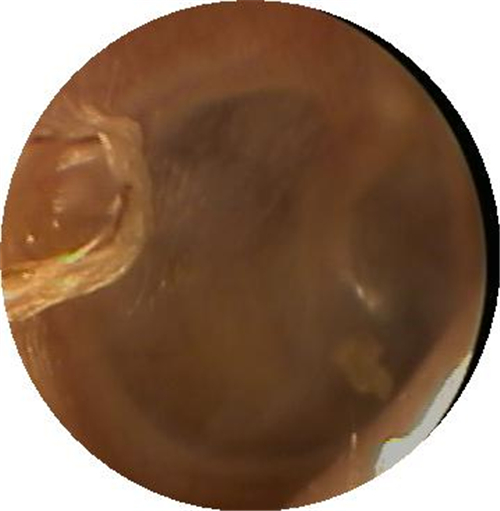

自愈的鼓膜穿孔